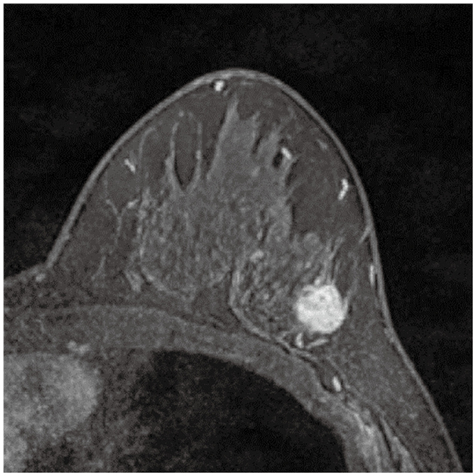

症例2

症例2の患者情報

20歳代,女性。

多発乳腺囊胞に対して経過観察中。乳房超音波検査で右乳房に増大する腫瘤を指摘され,精査のために乳房造影MRIを撮像した。